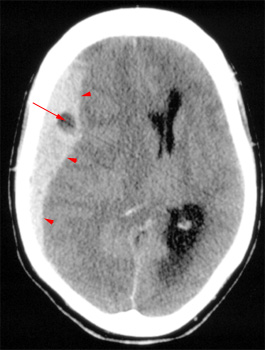

Head CT > Trauma > Acute Subdural Hematoma

Acute Subdural Hematoma

Deceleration

and acceleration or rotational forces that tear bridging veins can cause

an acute subdural hematoma. The blood collects in the space between the

arachnoid matter and the dura matter. The hematoma on CT has the following

characteristics:

- Crescent shaped

- Hyperdense, may contain hypodense foci due to serum, CSF or active bleeding

- Does not cross dural reflections